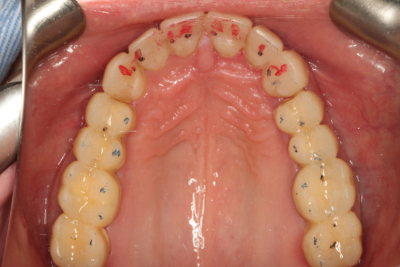

私たちの目標は常に、可能な限り最高の機能的結果を達成し、患者の目標を満たすために必要な最小限の歯科治療を行うことであるべきです。 ダレンは伝統的な歯科矯正に興味がなかったので、私たちは彼の機能の包囲の自由度を増加させ、前歯部咬合関係を改善するためにクリアアライナー療法から開始することを選択しました

歯科矯正はまた、歯の準備でより保守的にすることができました。 上顎切歯の舌側には、すでにかなりの歯質が磨耗していたため、削らなければならない歯質の量を最小限にしたかったのです。 また、矯正歯科では、前方誘導のために必要な下顎前歯の前処置や間接補綴を避けることができます。

矯正治療後、私たちは間接修復のために上顎弓を準備し、ダレンに仮の修復物を装着しました。 また、下顎切歯縁をダイレクトコンポジットで修復し、露出した象牙質を封鎖し、診断用ワックスアップから製作した熱可塑性ステントを用いて切歯面を整えました。 ステントを使用して切縁にダイレクトコンポジットを装着することで、時間を節約し、切縁の位置をより正確にすることができました。 その後、ダレンは歯周病専門医に送られ、歯肉の構造を修正しました。